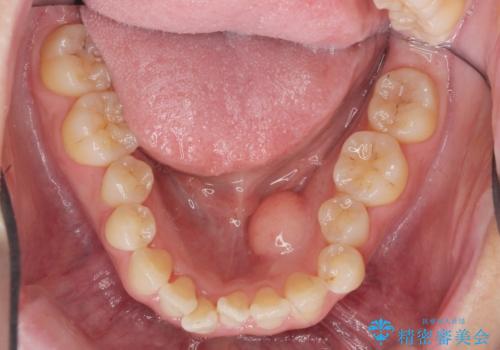

舌のスペースが広くなったと喜んでいただくことができました。

反対側も除去を予定しています。